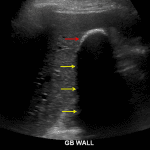

- Thickened, echogenic gallbladder wall with extensive corresponding posterior acoustic shadowing, which obscures much of the gallbladder

- The visualized pericholecystic spaces show no definite fluid or inflammatory changes

Porcelain gallbladder

Extensive mural calcification of the gallbladder (“porcelain gallbladder”), which is associated with an increased (but still low) risk for gallbladder adenocarcinoma. Although there are no specific findings for acute cholecystitis, the gallbladder is difficult to assess on this study and surgery consultation should be pursued if there are ongoing symptoms. If cholecystectomy is not performed, then followup surveillance imaging with contrast-enhanced CT or MRI is recommended in 6-12 months.